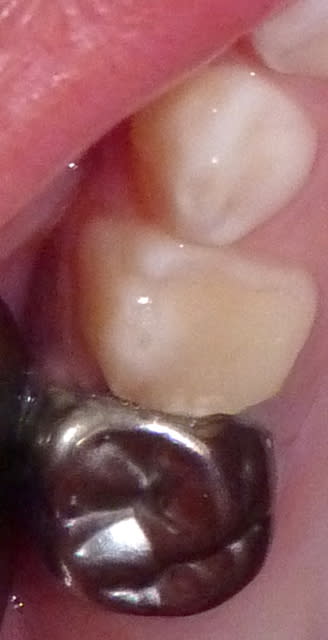

20/07/11 : secteur II.

Hygiène toujours très bonne sauf en postérieur des secteurs II/II car 75 très douloureuse. (Je ne me suis rendu compte qu'à la fin de la séance de la saleté en vestibulaire de 65: heureusement nettoyée avant scellement CPP !).

65 : Pulpo. Moignon CVI. CPP.

Fluoration.

23 qb9uiu - Eugenol

24 rcgkv0 - Eugenol

21 ytexa6 - Eugenol

22 mloic7 - Eugenol